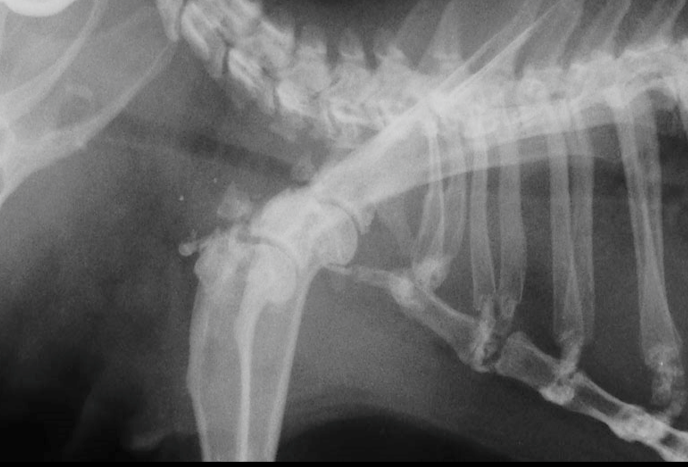

線維性骨異栄養症

骨が線維化を起こして脆くなる病態で、骨折を起こしやすくなります。通常の外傷による骨折とは発生の意味合いが異なります。線維性骨異栄養症を引き起こす原因として、副甲状腺機能亢進症(上皮小体機能亢進症)があげられ、過剰に副甲状腺ホルモン(PTH:parathormone:パラソルモン)が分泌された結果、骨に影響を与えます。モルモットの副甲状腺の裏側で甲状腺葉に囲まれて位置しています〔Zabel et al.1986〕。副甲状腺機能亢進症には副甲状腺自身の異常を原因とする原発性副甲状腺機能亢進症とカルシウム代謝の破綻を原因とする二次性副甲状腺機能亢進症とに区別され、モルモットでは後者の二次性副甲状腺機能亢進症が主です。副甲状腺ホルモンの過剰な分泌は、血中のカルシウム濃度が低下すると分泌が高まり、骨に含まれているカルシウムを血中に溶出させ、腎臓に作用してリンの再吸収を抑制し、カルシウムの再吸収を促して尿中への排泄を減らします。 また、腎臓におけるビタミンDの活性化を促進して、活性型ビタミンDの作用によって腸管からのカルシウムの吸収を増加させます。骨のカルシウムを血液中に溶出させることから、骨が線維化を起こして、骨痛や骨変形・病的骨折などの原因となります〔Hawkins et al.2012〕。また、過剰な副甲状腺ホルモンは、身体の様々な場所へのカルシウムを沈着(異所性石灰化)させたり、心臓血管系、胃腸腸管、胆嚢、気管、子宮および精管の平滑筋の弛緩も引き起こすと言われています〔Motomura et al.1998,Kline et al.2000〕。二次性副甲状腺機能亢進症は幼体に好発する栄養性副甲状腺機能亢進症と中高齢に好発する腎性副甲状腺機能亢進症があげられます。栄養性副甲状腺機能亢進症はカルシウムとリンの摂取量が不均衡、ビタミンDの不足が原因です。しかし、モルモットにおける明確な文献などの報告は少なく、これまでの報告では10ヵ月齢のメス、2歳のオス、1歳のオスのモルモットで発生した例があるに過ぎません〔Rapsch et al. 2009,Schwarz et al.2001〕。腎性副甲状腺機能亢進症は慢性腎不全になりやすい中高齢にみられ、腎臓でのリンの排泄およびビタミンD3の活性化ができなくなります。また活性化ビタミンD3が低下すると、腸管からのカルシウムの吸収が低下します。